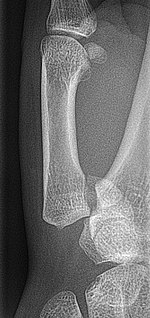

Boxer's fracture Boxers fracture at the neck of the fifth metacarpal punching solid object Boxer's fracture Archived 2007-07-15 at the Wayback Machine at Wheeless' Textbook of Orthopaedics online Fractured5thMetacarpalHead2018.jpg